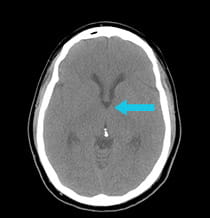

pre-surgical scan shows a colloid cyst of the third ventricle post-surgery scan showing completely removed colloid cyst

Scan after surgical procedure shows complete removal of colloid cyst.

The colloid cyst was completely removed using the minimally invasive Neuroendoport technique.

The patient's cognition and headaches improved immediately, and the fainting spells are gone. In the follow-up image, which was performed while the patient was still in the operating room, it is clear that the colloid cyst has been completely removed. Intra-operative imaging with a CT scanner allows UPMC neurosurgeons to confirm safe lesion resection prior to leaving the operating room.